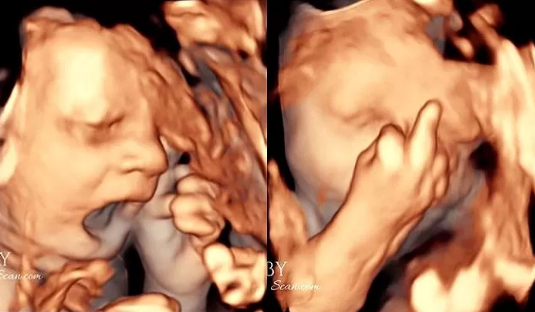

さらに、顔からも不満げな姿が映し出されており、胎児が思いっきりあくびをしています。その後、身体を隠し始めたというので、もしかすると「恥ずかしいからこれ以上見ないでくれ」という意思表示なのかもしれませんが、両親は意外にも好意的。性別は男の子ということですが、「早く生意気な我が子に会いたい」とのこと。

また、このような仕草は妻いわく「夫に似ている」とのこと。そのため、完全に遺伝子を受け継いでいるのかな、といった印象ですが、過去にも別の胎児がピースサインをしていたという記事が話題になったりもしたので、赤ちゃんというのは生まれる前から本当に不思議な行動をすることがあるんだな、と思わざるをえませんね。